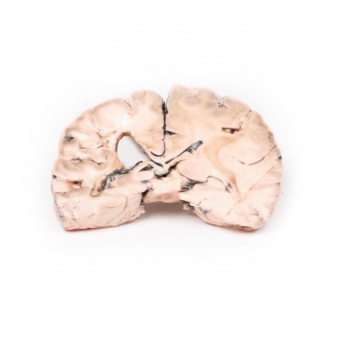

Hirninfarkt links

Ein koronaler Schnitt der Hirnhemisphären zeigt unregelmäßige zystische Hohlräume im Versorgungsgebiet der rechten mittleren Hirnarterie. Die Hohlräume des Infarkts haben unregelmäßige, gelbe Wände und weisen einen teilweisen Kollaps auf. Der linke Seitenventrikel weist eine kompensatorische Dilatation auf. Auf der hinteren Seite waren die Arterien unterhalb der Mammillarkörper mäßig atheromatös, obwohl dies makroskopisch schwer zu erkennen ist.

Aufgrund der zugrundeliegenden Myokarderkrankung mit dem Vorhandensein des Wandthrombus wird angenommen, dass ihr Hirninfarkt wahrscheinlich durch ein Thromboembolus verursacht wurde.